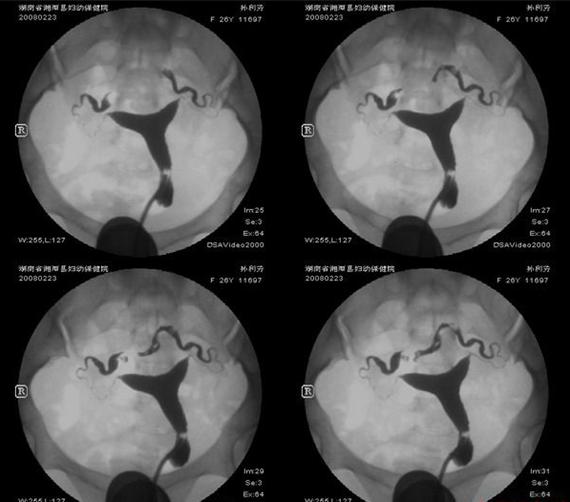

她39歲,38歲胎死腹中後一直不孕,原來是子宮沾黏,輸卵管阻塞,難怪她不孕!在博元婦產科一次試管嬰兒成功,生下一名男寶寶 不孕症(1)39歲 (2)不孕症兩年 (3)曾經生過一個小孩子,在38週胎死...

她輸卵管阻塞,做了3次試管嬰兒都失敗,轉到博元婦產科,先以腹腔鏡手術,再做試管嬰兒,竟3胞胎 不孕症: 雙邊輸卵管阻塞 ...